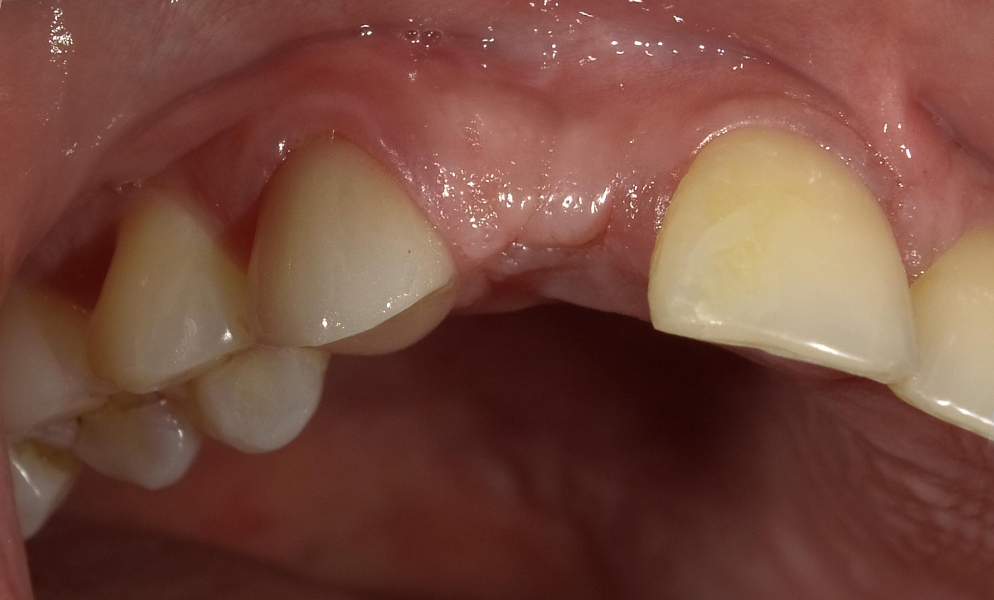

| Before | After |

![]() |

| Single anterior tooth missing space restored with a narrow dental implant (Bicon, USA) | |